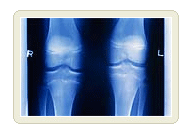

뼈에 구멍이 생기는 질병 골다공증

(骨多孔症,:osteoporosis)

골다공증은 뼈의 무기질과 단백질 감소로 골조직이 엉성해지는 증상으로 일본은「골조송증(骨粗송症)」으로 부르며 유럽은「오스테오포로시스:osteoporosis)」라고 부르는데 골다공증 즉 뼈에 구멍이 가득한 질병으로 표시한다. 등뼈 내부는 세로로 뻗은 뼈와 가로로 뻗은 뼈가「수세미」와 같은 모양을 이루고 있는데 이를 해면골(海綿骨)로 부른다.

골다공증에 걸리면 어떤 증상이 나타나는가. 등뼈를 측면에서 바라보면 척추 하나 하나는 사각(四角)을 이루고 칼슘이 채워져 있는데 나이를 먹으면 내용물이 줄어든다. 그러면 체중 지탱이 불가하여 앞부분 손상으로 사각 뼈가 쐐기모양으로 된다.

장기간 칼슘부족이 지속되면 여기 저기에서 뼈가 용해된다. 구멍이 몇 개 발생한 단계에서 치료하면 원상태로 되돌릴 수가 있다. 그러나 더 진행되어 뼈에 띄엄띄엄 구멍이 뚫리면 원상태로 되돌릴 수가 없게 된다.

뼈는 구조역학적으로 신체를 지지하는데 뼈로서의 기능을 전혀 수행하지 못하게 된다.